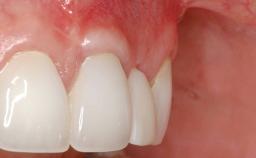

Soft-Tissue Volume Augmentation Using a Connective-Tissue Graft Harvested from the Maxillary Tuberosity